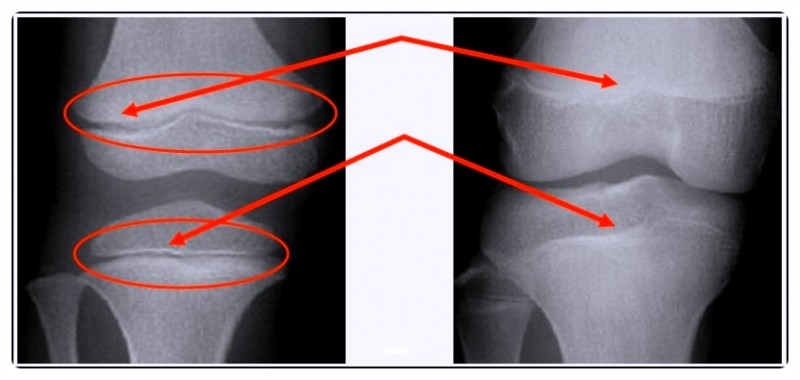

성장은 단순히 뼈가 길어지는 과정이 아닙니다.

뼈와 근육, 인대의 균형이 함께 맞아야 건강한 성장이 이뤄지죠.

하지만 잘못된 자세나 걸음걸이로 인해 성장판에 지속적인 압력이 가해지면, 성장 속도가 늦어질 수 있습니다.

요즘 아이들은 스마트폰 사용과 오랜 책상 생활로 척추나 골반이 틀어진 경우가 많습니다.

이렇게 체형이 불균형하면 성장호르몬이 충분히 분비돼도 그 에너지를 효율적으로 활용하기 어렵습니다.